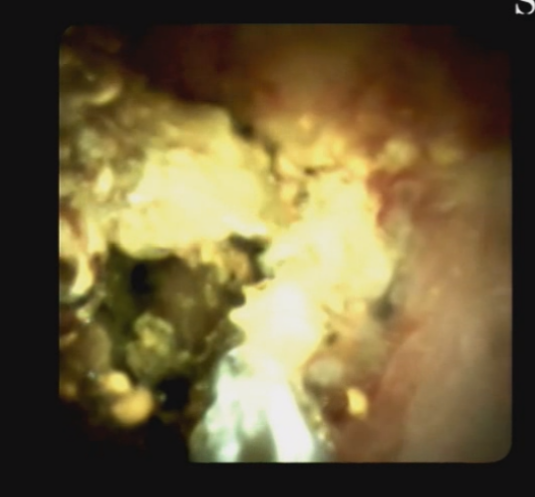

另外,經(jīng)口膽道子鏡光纖直視系統(tǒng)(SPYGLASS)是一種電子膽道子鏡,可通過(guò)十二指腸鏡到達(dá)膽管或胰管內(nèi),對(duì)病變進(jìn)行直視觀察,高清高分辨率顯示病變、并精準(zhǔn)指導(dǎo)活檢,對(duì)于膽胰管狹窄的診斷治療具有重要意義。

5466bc1aa2b44eeabb2f6ab4904c0f6c.Png  0c9bb25f31ed492197b787eecbde3974.Png

經(jīng)口膽道鏡下膽總管碎石